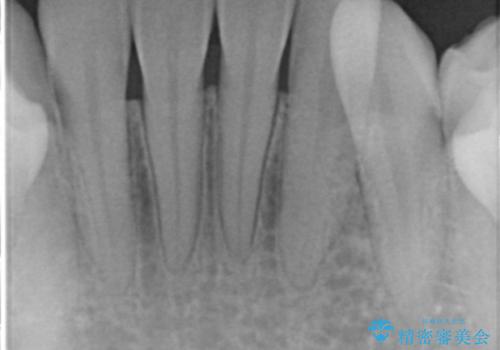

矯正治療を行う前には、虫歯や歯周病の問題を解決しておかないと矯正治療を行なっている最中や治療後に大きな問題となって返ってこないよう治療前に問題を解決しておくことが重要です。

初診時、下顎前歯にびっしりとついていた歯石を除去することで歯肉の発赤・腫脹は治まり健康な状態になることができました。